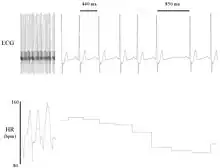

Heart rate variability (HRV) is the physiological phenomenon of variation in the time interval between heartbeats. It is measured by the variation in the beat-to-beat interval.

Other terms used include "cycle length variability", "R–R variability" (where R is a point corresponding to the peak of the QRS complex of the ECG wave; and R–R is the interval between successive Rs), and "heart period variability".[1] Measurement of the RR interval is used to derive heart rate variability.[1]